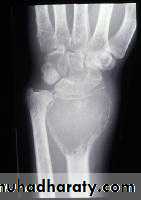

Giant cell tumour

= osteoclastomaBenign but locally aggressive

Histology : abundant multinucleated giant cellsAge : 20-40 yr

Site : around the knee

distal radius

Metaphyseal-epiphyseal

XR : soap – bubble appearance

Rx : curettage + tumouricidalHi recurrence rate

Malignant potential : 5%Osteosarcoma